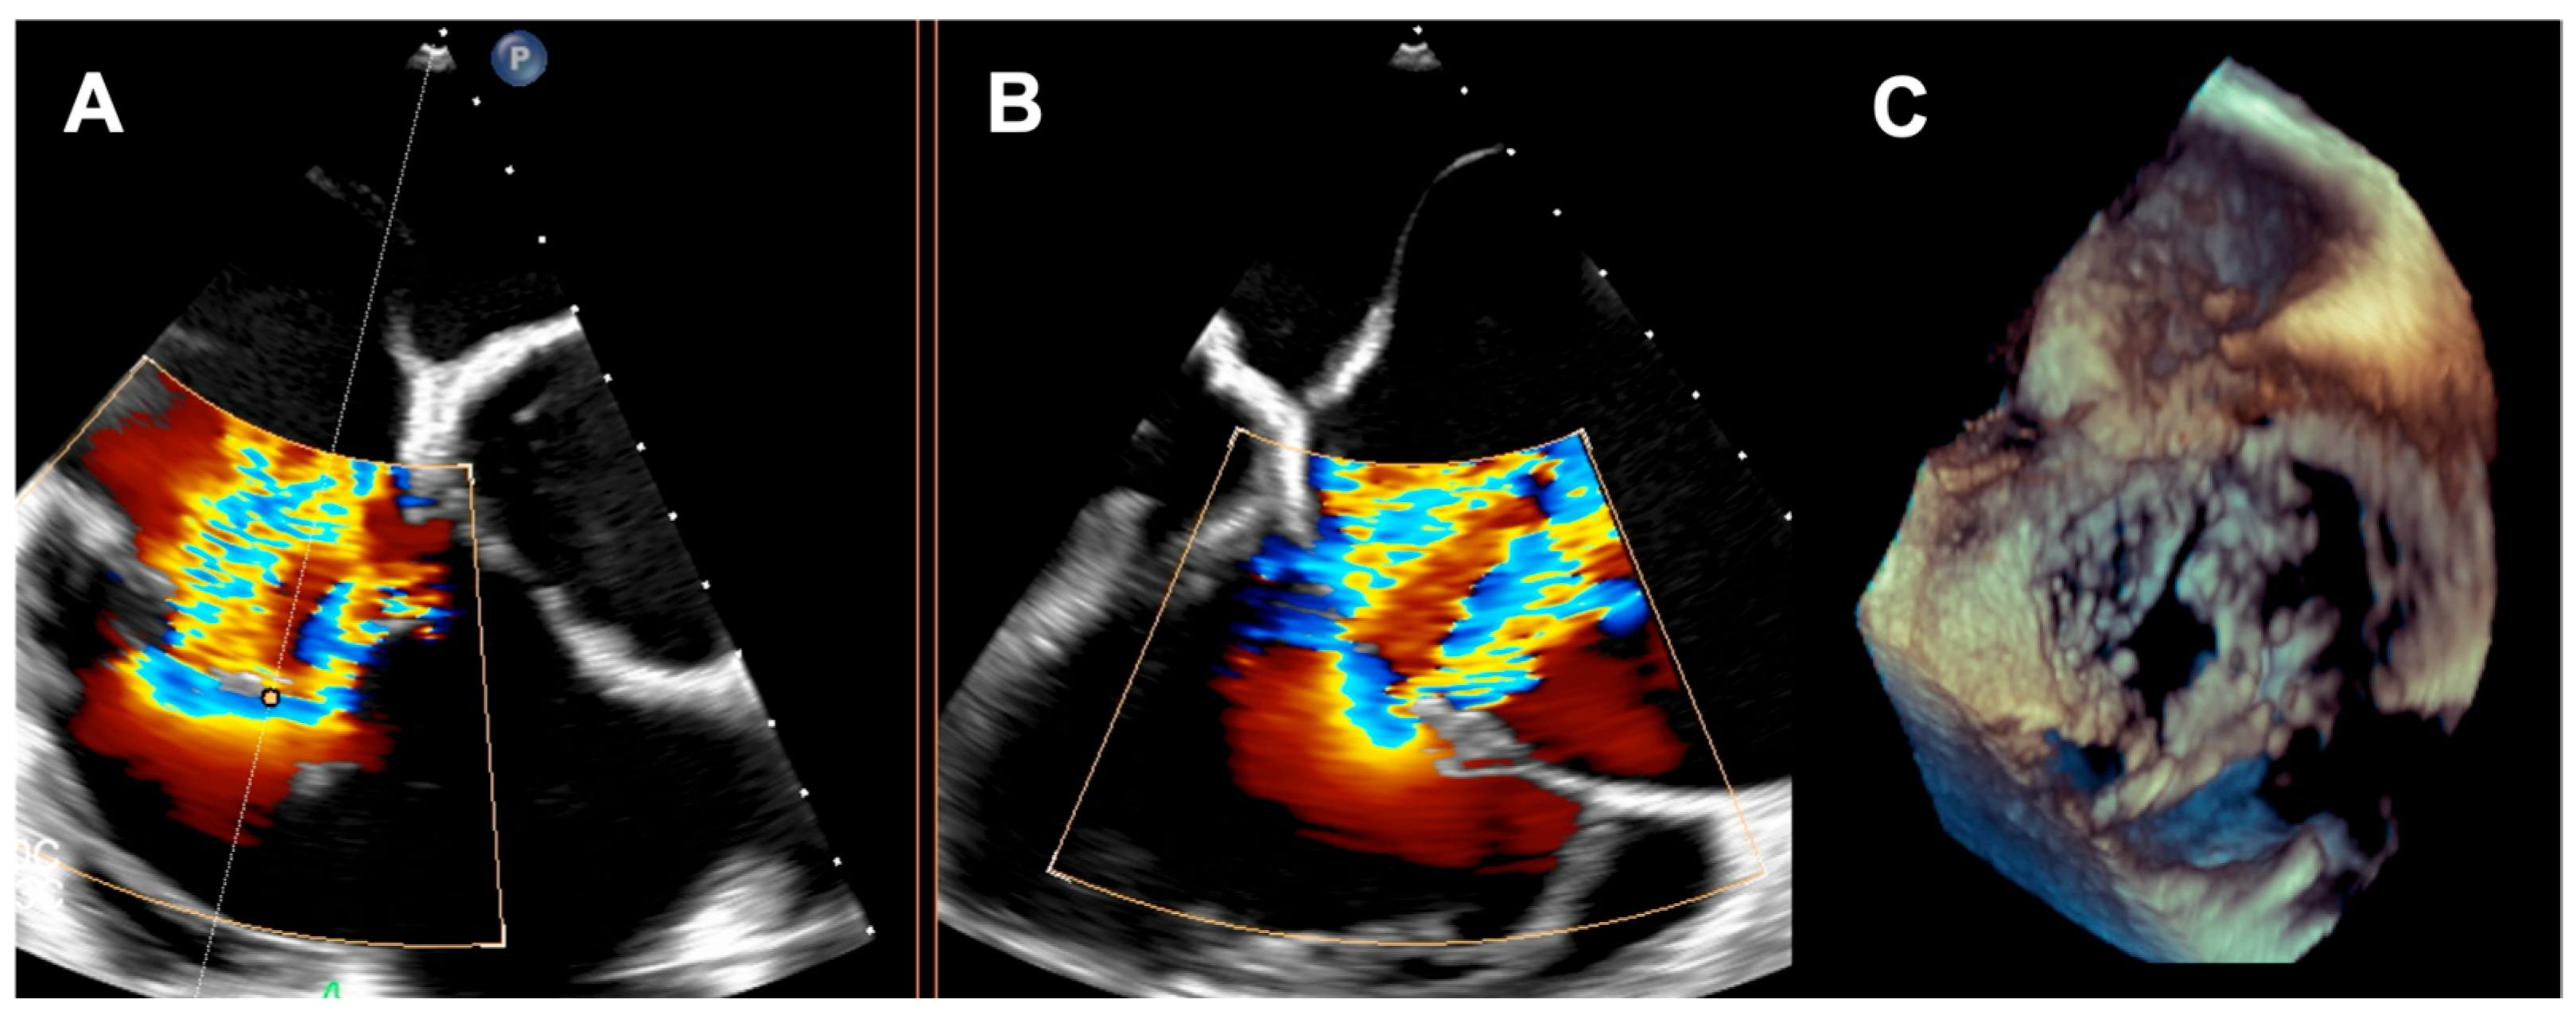

The first patient was a 77-year-old woman who had persistent heart failure symptoms (HF) in NYHA class III due to torrential regurgitation of the tricuspid bioprosthesis (CoreMatrix) that was implanted five years before. (Figure 1) The patient’s past medical history included a myocardial infarction 15 years before, coronary artery bypass grafting 15 years before, permanent atrial fibrillation, peripheral artery disease, type 2 diabetes, chronic kidney disease, and implantation of a leadless pacemaker. The patient suffered from recurrent exacerbations of HF that required hospitalization despite intensive diuretic treatment in the preceding year. Due to the very high predicted mortality risk (Table 1) and the history of two previous cardiac surgeries, the patient refused surgical treatment. Because the anatomy of the degenerated tricuspid bioprosthesis was not suitable for edge-to-edge treatment, the patient was offered the CAVI procedure. Valves of the TricValve system were implanted in the superior cava (SVC) and inferior vena cava (IVC), respectively, 21 mm and 41 mm. (Figure 2) The procedure was complicated, with access site bleeding requiring surgical intervention. The patient’s echocardiography, post their procedure, revealed a mild paravalvular leak in the IVC valve. One month after the procedure, the patient persisted in NYHA functional class II; however, during the following months, she was hospitalized due to exacerbation of their right ventricular failure. Eventually, the patient died 9 months after the procedure because of the progressive worsening of right ventricular dysfunction and multiorgan failure.

Figure 1. (A) Degenerated tricuspid CoreMatrix bioprosthesis; (B) torrential tricuspid regurgitation.